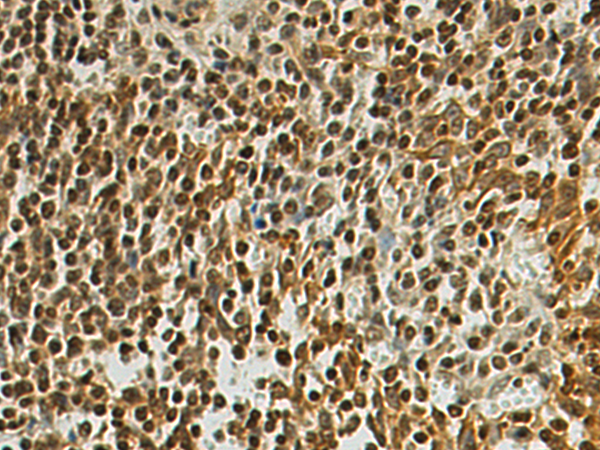

DIP2A |

Fusion protein of human DIP2A |

IHC positive control: |

Human colorectal cancer and Human tonsil |

IHC Recommend dilution: |

100-300 |